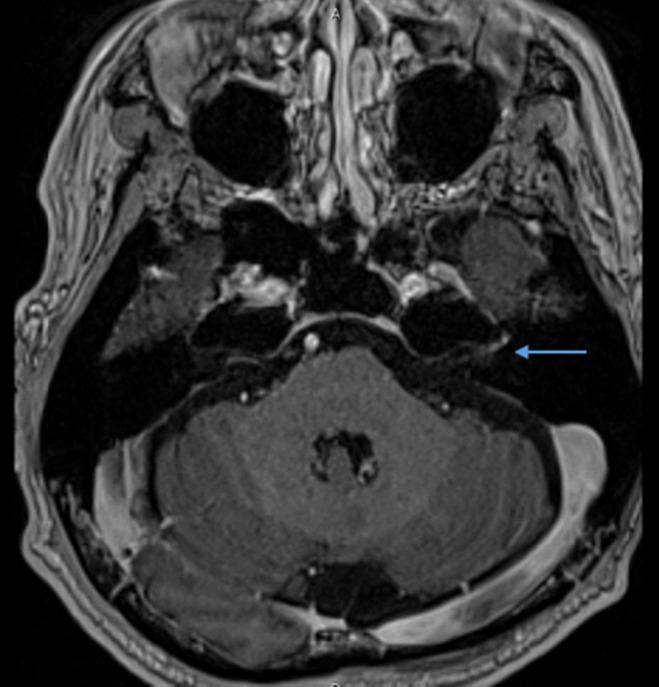

CASE PRESENTATION

A man with renal cell carcinoma who received rechallenging immune checkpoint inhibitor therapy developed unilateral facial palsy and was diagnosed with Bell's palsy. He did not have any severe immune-related adverse events during his previous immune checkpoint inhibitor treatment. Corticosteroid therapy was immediately initiated, and his facial palsy symptoms promptly improved.

外周神经系统是免疫相关不良事件的靶器官之一。由免疫检查点抑制剂诱发的周围性面神经麻痹,也称为贝尔麻痹,非常罕见,其临床特征尚不清楚。

病例介绍

一名接受再次免疫检查点抑制剂治疗的肾细胞癌男性出现单侧面神经麻痹,并被诊断为贝尔麻痹。他在之前的免疫检查点抑制剂治疗期间没有发生任何严重的免疫相关不良事件。立即开始使用皮质类固醇治疗,其面神经麻痹症状迅速改善。